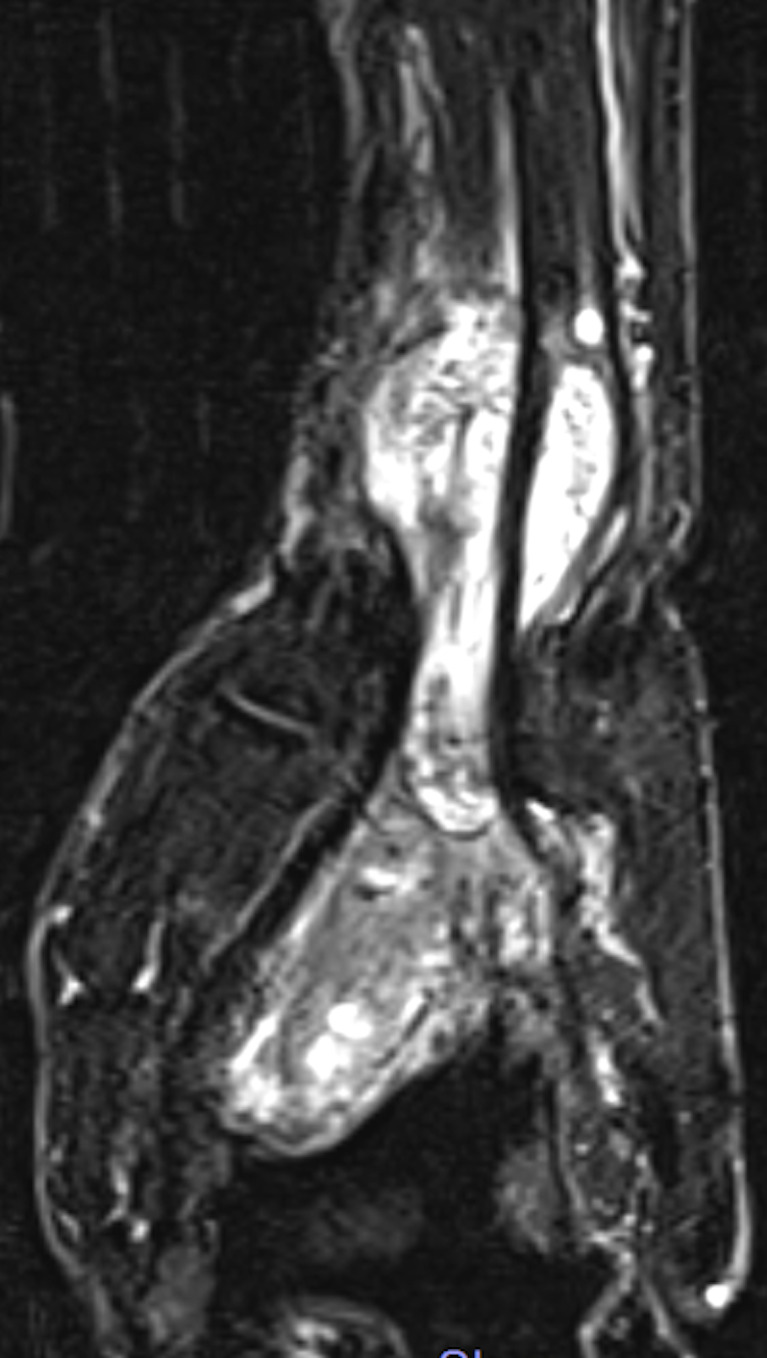

Granulomatous flexor tenosynovitis due to Mycobacterium intracellulare.

由胞内分枝杆菌引起的肉芽肿性屈肌腱滑膜炎。